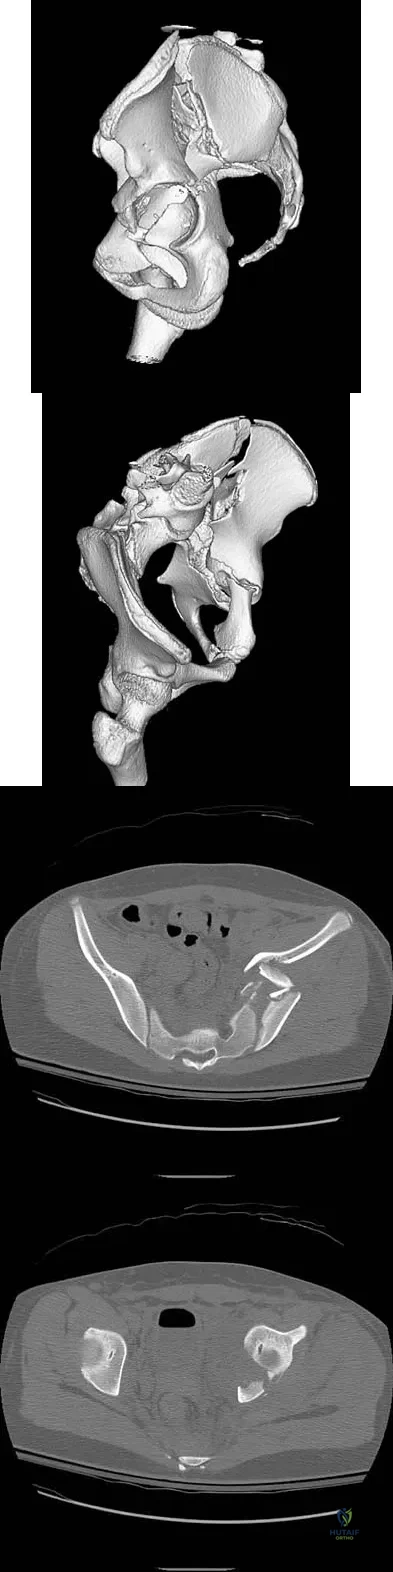

A 43-year-old woman has had pain in the left hip for the past 2 months. A radiograph, CT scan, MRI scan, and biopsy specimens are shown in Figures 16a through 16e. What is the most likely diagnosis?

A 13-year-old girl was riding on an all-terrain vehicle when the driver struck a tree. She sustained the injury shown in Figures 45a through 45d. This injury is best described as what type of acetabular fracture pattern?

Explanation